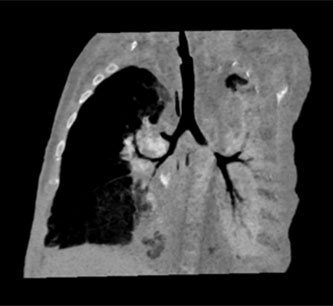

CT显示左主支气管局部狭窄近乎闭塞

经过NICU(新生儿重症监护室)的积极抢救,并在2014年12月5日行房间隔缺损修补术后,小宝宝心脏脱险了,但他仍反复肺部感染,无法脱离呼吸机的支持自由呼吸,气管镜检查发现左主支气管近端重度狭窄,胸部CT同样提示左肺发育不良,明显缩小,左主支气管局部狭窄近乎闭塞。怎么办?难道要让宝宝一直带着气管插管和呼吸机生存?